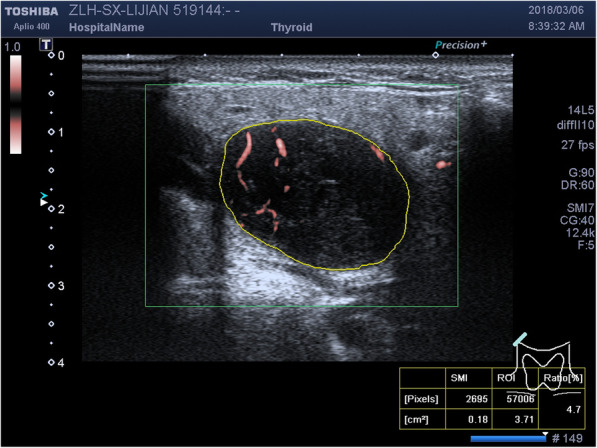

Vascular index (VI): shown in Fig. 1, after cSMI images were taken, manually trace the boundary of the tumor, and the recorded the whole tumor was regarded as the ROI, and the system automatically calculated the VI with in the described area. VI refers to the ratio between the pixel of doppler signal and the pixel of the whole lesion. Each tumor was recorded 3 times and averaged.

Fig. 1.

Trace the ROI and calculate VI by cSMI of a WT case